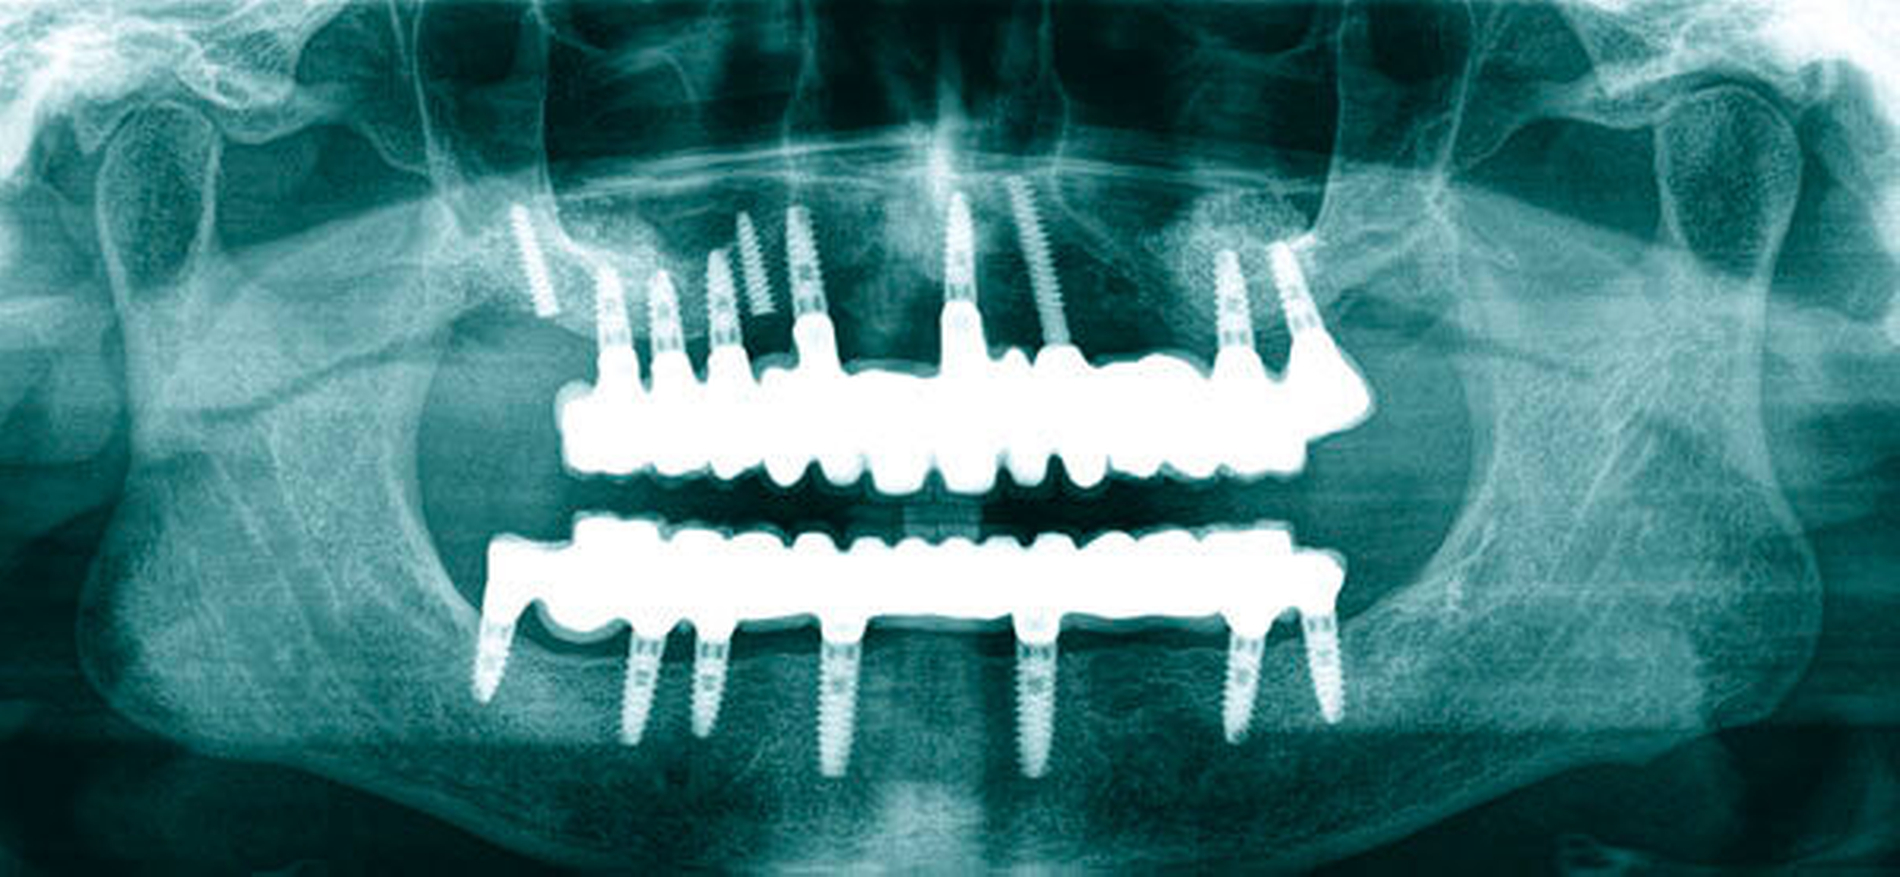

Die chirurgische Platzierung von Zahnimplantaten, das heißt die eigentliche Implantation, und die nachfolgende prothetische Versorgung dieser Implantate liegen nicht immer in einer Hand, sondern werden zum Teil von zwei verschiedenen Behandlern durchgeführt. Eine solche Arbeitsteilung hat durchaus Vorzüge: Aus der Allgemeinchirurgie wissen wir, dass Operateure mit großer Behandlungsroutine (hohe Fallzahlen pro Jahr) signifikant bessere Ergebnisse erzielen [Halm et al., 2002]. Doch geteilte Zuständigkeiten bergen auch Fallstricke: Wenn die Implantation und die nachfolgende prothetische Versorgung nicht gemeinsam geplant oder zumindest aufeinander abgestimmt werden, stellen sich im Fall eines ungünstigen Endresultats (Behandlungsfehler-Vorwurf) Fragen der Verantwortlichkeit. Man denke etwa an einen Fall, in dem ein Fachchirurg Implantate setzt, die aus Sicht des Implantatprothetikers falsch positioniert sind (Abbildungen 1, 2, 4, 5 und 6).

Letzterem bleibt nur die Wahl zwischen der Ablehnung der Weiterbehandlung und der Empfehlung einer aufwendigen und substanzverlustträchtigen Revision der Implantate (beides mutet dem betroffenen Patienten einiges zu) oder einer „Kompromissbehandlung“ mit dem Ziel, die invasive Revision der gesetzten Implantate abzuwenden und so den Schaden für den Patienten zu begrenzen. Heikel wird es insbesondere dann, wenn der Prothetiker in bester Absicht eine solche Kompromissbehandlung wagt, diese sich aber als nicht alltagstauglich erweist und der Patient schlussendlich Klage erhebt.

Hier kann es unter Umständen schwerfallen, die Verantwortung zuzuweisen: Liegt die Schuld beim Chirurgen, der die Implantate an ungünstiger Stelle gesetzt hat, oder beim Prothetiker, der sich nolens volens auf diese Situation eingelassen und ein letztlich unzureichendes Behandlungsergebnis erzielt hat? Aus fachlicher und ethischer Sicht ist die eigentliche Ursache für das insuffiziente Behandlungsergebnis beim Chirurgen zu suchen. Juristisch gesehen trägt dagegen jedoch der Implantatprothetiker die unmittelbare Verantwortung für das Behandlungsergebnis, da er die insuffiziente Suprakonstruktion geplant und eingegliedert hat. Rechtlich verhängnisvoll wird dieses Vorgehen insbesondere dann, wenn er den Patienten nicht explizit über den Kompromiss- und Versuchscharakter seiner Versorgung aufgeklärt hat oder das Aufklärungsgespräch und das Einverständnis des Patienten zur eigenen juristischen Absicherung nicht sorgsam dokumentiert hat.